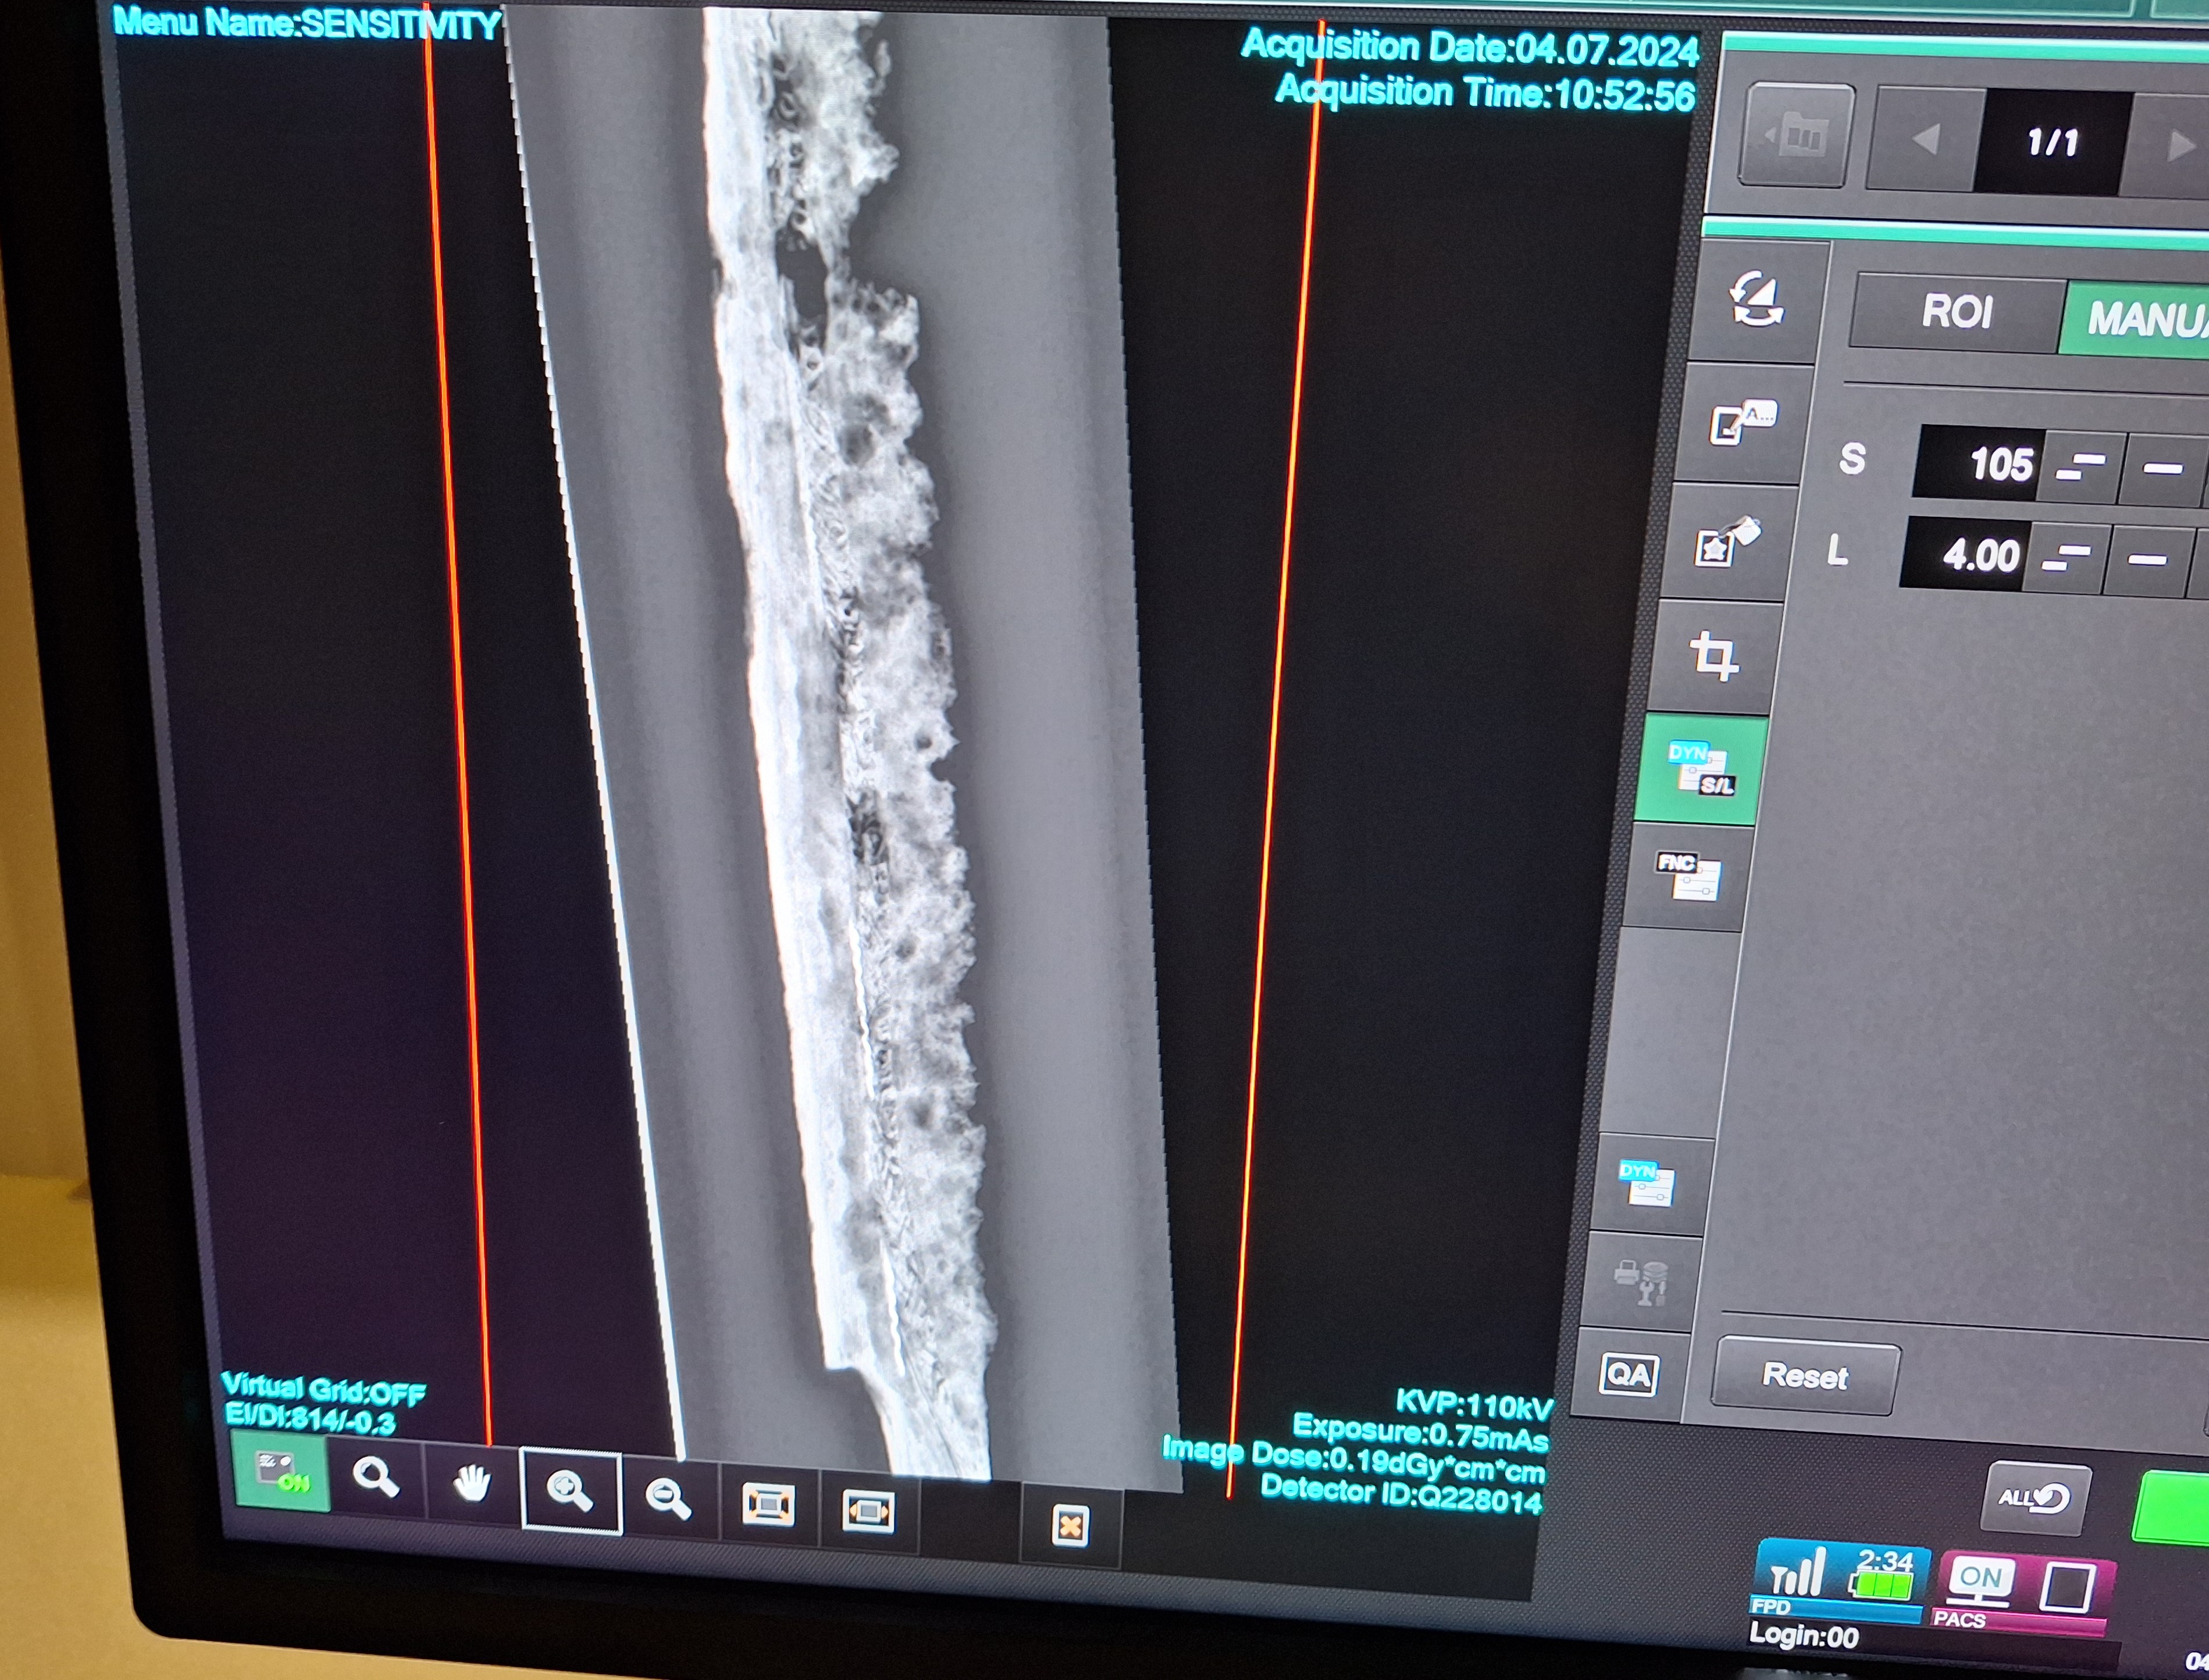

Senior lecturer in diagnostic radiography at the university, Christopher Cobb, will X-ray a variety of items from the museum’s collection in the radiography suite.

Full results are yet to be published, but early findings have revealed the mammoth may have had an illness which severely impacted the last years of its life.

Meanwhile the Anglo-Saxon fighting knife – known as a seax – had an intricate pattern that would have been visible on the surface, indicating it was owned by someone of high status.

Dr Simon Jackson, collections and learning curator at Colchester and Ipswich Museums, said: “X-ray analysis is a powerful tool to help us look beneath the surface of our objects and into their very fabric and nature. Although the technology has been around now for several decades, recent advances in X-ray technology allow far more detail to be seen.

“The results of the tests at the University of Suffolk clearly show the potential of this technology in helping us to more fully understand them. Undoubtedly more secrets are locked away in our collections waiting to be discovered.”

(Image: One of the mammoth vertebrae that was X-rayed in the collaboration, via Colchester + Ipswich Museums Service)